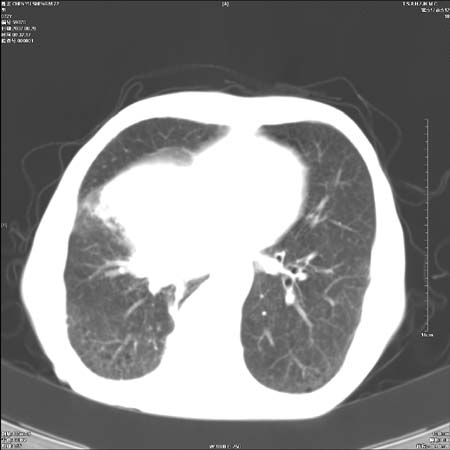

男性,72岁,既往肺结核,今复查。无前片对比。

右侧中央型肺癌伴中叶不张可能性大,建议增强扫描.右上肺陈旧性肺结核.慢性支气管炎伴肺气肿.右侧少量胸腔积液.

中心性肺癌肺转移

右侧中央型肺癌伴中叶不张可能性大,建议纤支镜检查.右上肺陈旧性肺结核.肺气肿。

典型右肺中心型肺癌

右侧中央型肺癌伴肺不张可能性大,建议增强扫描.右上肺陈旧性肺结核.慢性支气管炎伴肺气肿.右侧少量胸腔积液.

右肺中心型肺癌

右侧中央型肺癌.上肺陈旧性肺结核.

1右侧中央型肺癌伴中叶不张2右侧少量胸腔积液3右上肺陈旧性肺结核

1.右肺中心性肺癌并右肺中叶综合征2。右侧胸腔少量积液3。右肺上叶结核球已钙化,4。慢支伴肺气肿

右侧中央型肺癌伴中叶不张可能性大,建议纤支镜检查.右上肺陈旧性肺结核.肺气肿。

右侧中央型肺癌伴中叶不张可能性大,建议增强扫描.右上肺陈旧性肺结核.慢性支气管炎伴肺气肿.右侧少量胸腔积液.

右侧中央型肺癌伴中叶不张

右肺中央型肺癌伴右肺中叶不张。

右上肺陈旧性肺结核。

支持右肺中心型肺癌并中叶不张,右上肺陈旧性肺结核钙化,右侧少量胸腔积液。

支持右侧中央型肺癌伴中叶不张可能性大,建议增强扫描.右上肺陈旧性肺结核.慢性支气管炎伴肺气肿.右侧少量胸腔积液.

右侧中心型肺癌可能性大.肺气肿.胸腔积液.

支持 1右侧中心型肺癌伴中叶不张2右侧少量胸腔积液3右上肺陈旧性肺结核4双肺局限性肺气肿

1,右侧中央型肺癌.

2,右上肺陈旧性肺结核.

1.右侧中央型肺癌伴中叶不张,建议纤支镜检查.

2.右上肺陈旧性肺结核.

3.肺气肿。

4.右侧少量胸腔积液.

右侧中央型肺癌伴中叶不张并纵隔淋巴结增大,建议增强扫描.右上肺陈旧性肺结核.慢性支气管炎伴肺气肿.右侧少量胸腔积液。

右肺中心型肺癌并肺不张,陈旧性肺tb.慢支,肺气肿.

陈旧性肺结核.慢性支气管炎伴肺气肿,中央型肺癌伴中叶不张。

右侧中央型肺癌伴中叶不张可能性大;右上肺陈旧性肺结核.慢性支气管炎伴肺气肿

陈旧性结核是存在,但真正致命的却是右侧中心型肺癌。